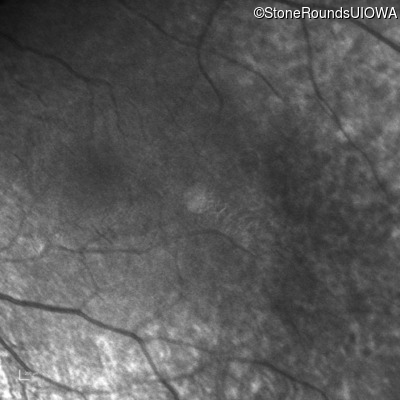

Infrared Fundus Photograph - Left -

No Light Perception

Exemplar

Light Perception